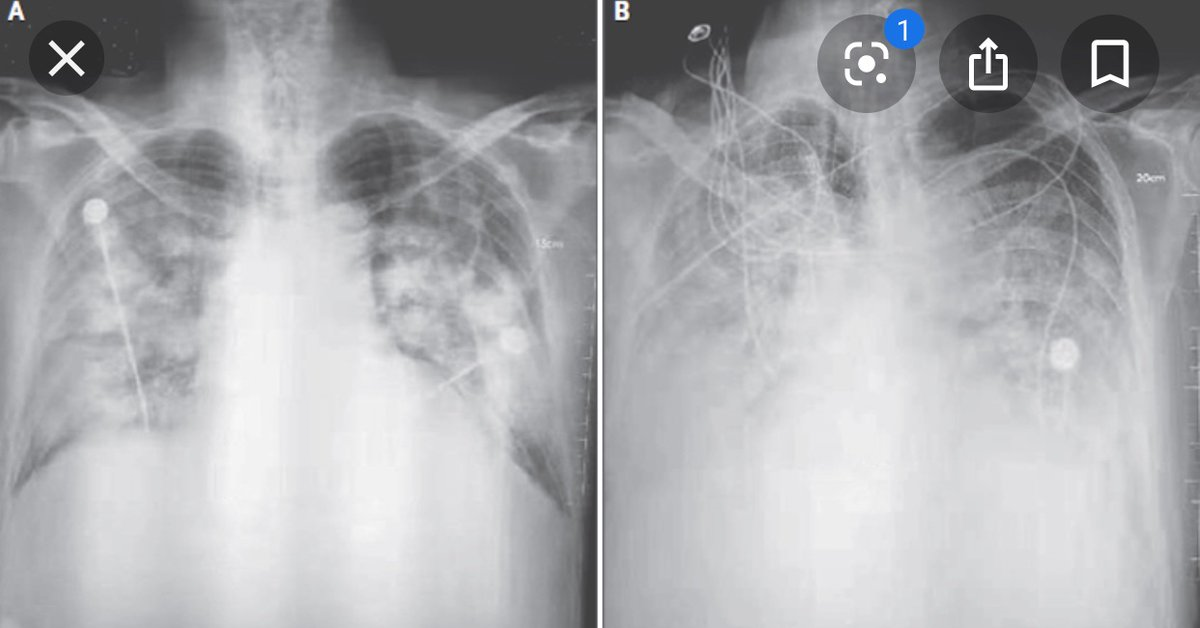

در نخستین روزهای شیوع کرونا عکسهایی واقعی و غیرواقعی از ریه مبتلایان منتشر شد و ترس عمومی را برانگیخت. برای بسیاری این تصاویر به احتمال نابودی کامل ریه تعبیر شد!

امکان بازگشت ریهها به حالت عادی

بررسی وضعیت پزشکی مبتلایان به کرونا پس از بهبودی، از همان ماه نخست شیوع جهانی کرونا نشان داد عوارض این بیماری تا مدتی باقی میماند. یکی از نخستین تحقیقات دراینباره در هنگکنگ نشان داد عوارض ریوی مهمترین مشکل مبتلایان پس از بهبودی است. محققان این کشور متوجه اختلال در عملکرد ریهها مبتلایان حتی پس از بهبودی کامل شدند. از همان ابتدای شیوع کرونا نیز مشخص شد ظرفیت ریههای افراد بهبودیافته کمتر از قبل شده است و برای برخی کسانی که به کرونای شدید مبتلا شده بودند تنها ۲۰ تا ۳۰ درصد ریهها عملکرد مطلوب داشت. بااینحال پزشکان حدس میزنند این مشکل با استفاده از روشهای مختلف از جمله فعالیت بدنی متناسب، قابل رفع است و ظرفیت ریهها به حالت عادی باز میگردد. کرونا در برخی بیماران به ریهها آسیبهای بیشتری هم میزند که با گذشت زمان میتوان دریافت ماندگار هستند یا خیر. اغلب عفونتهای ریوی باکتریایی هستند و قابل درمان. ولی وقتی عفونت ویروسی باشد موضوع پیچیدهتر میشود و وقتی پای ویروس ناشناخته کرونا در میان است دیگر باید منتظر گذشت زمان و بررسیهای دقیقتر پزشکی شد.